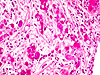

CASO N° 1 (Dr. Jair e Dr. Delgado)

Paciente do gênero masculino, 44 anos de idade, apresenta uma lesão no palato duro e palato mole.